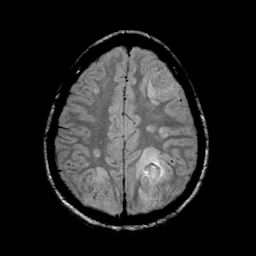

Sarcoma, MR Study #1 mr-pd -- Slice #18

[Home][Help][Clinical] Slice 18